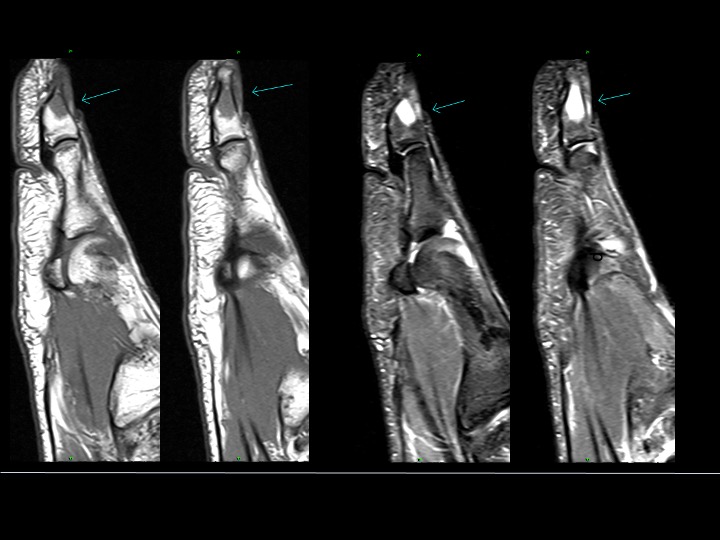

Quick Consult. Shoulder MRI. 62F 3_4 months pain and limited range of motion

There is band-like segmental infraspinatus > teres minor edema with mild infraspinatus atrophy in the same distribution. Can Parsonage Turner be so segmental within any given muscle? What else can this be? (There is also mild to moderate superior cuff tendinosis without tear, not shown). [image: 1.jpg] [image: 2.jpg] [image: 3.jpg] [image: 4.jpg] Feel free […]